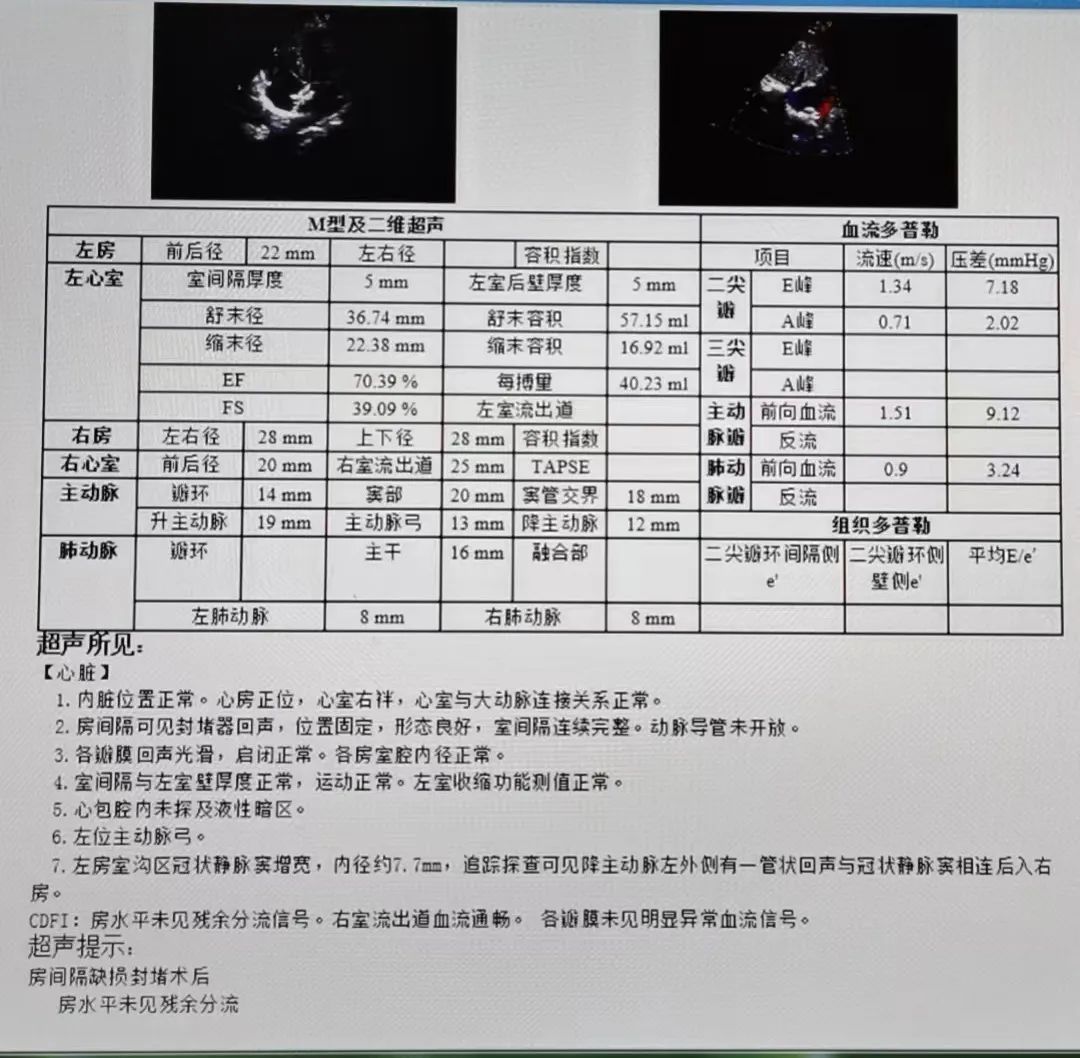

超声所见:

1.内脏位置正常。心房正位,心室右袢,心室与大动脉连接关系正常。

2.房间隔可见封堵器回声,位置固定,形态良好,室间隔连续完整。动导管未开放。

3.各瓣膜回声光滑,启闭正常。各房室腔内径正常。

4.室间隔与左室壁厚度正常,运动正常。左室收缩功能测值正常。

5.心包腔内未探及液性暗区。

6.左位主动脉弓。

7.左房室沟区冠状静脉窦增宽,内径约7.7mm,追踪探查可见降主动脉左外侧有一管状回声与冠状静脉窦相连后入右房。

CDFI:房水平未见残余分流信号。右室流出道血流通畅。各瓣膜未见明显异常血流信号。

超声提示:房间隔缺损封堵术后,房水平未见残余分流。